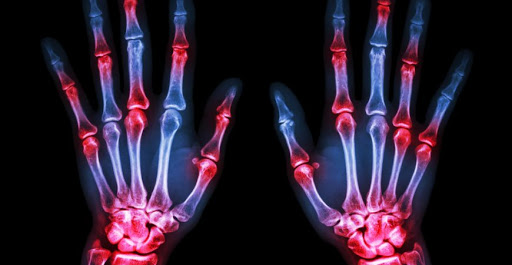

Коронавирусээр үүсгэгддэг КОВИД-19 урт хугацааны эмчилгээ шаарддаг үе мөчний асуудалд хүргэдэг байж болзошгүй гэж АНУ-ын Баруун Умардын их сургууль, “Northwestern Medicine” сүлжээ эмнэлгийн судлаачид үзэж байна.

Тэд халдвар авсны дараа үе мөчний хэрх үе судлалын эмчид хандаж байсан өвчтөнүүдэд судалгаа хийжээ. “Skeletal Radiology” сэтгүүлд мэдээлснээр, үе мөч, булчин өвдөх нь аутоиммун хариу үйлдэлтэй холбоотой гэж шинжээчид тогтоосон байна.

Коронавирус бие организмыг өөрөө өөр рүүгээ халдахад хүргэдэг бөгөөд энэ нь эрт хугацааны эмчилгээ шаарддаг үе мөчний өвчин үүсгэдэг байх талтай гэж судлаач Свати Демшук онцолжээ. Түүний хэлснээр, өвдөх мэдрэмж биеийн янз бүрийн хэсэгт үүсдэг байна. Зарим өвчтөнүүдийн хувьд мэдрэлийн эсүүд нь гэмтсэн байсан бол зарим өвчтөнүүдийн цусны эргэлт алдагдсан зэрэг шинж тэмдэг илэрчээ.